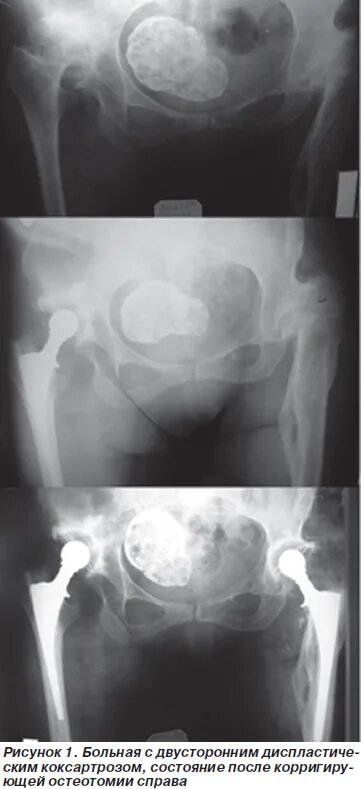

При коксартрозе дают инвалидность